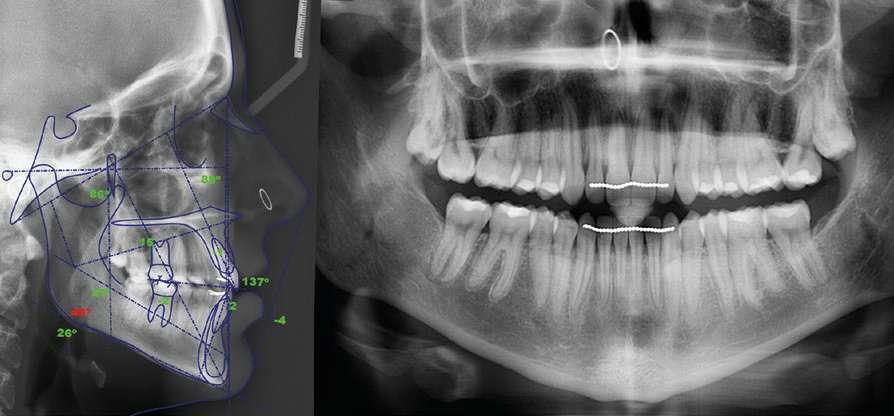

3.- Análisis radiográfico

- En la radiografía panorámica se puede observar (Fig. 4):

 Dentición permanente.

 Presencia de 18 y 28.

 Ausencia de patología ósea.

- Tras realizar el análisis de la cefalometría lateral de Ricketts y el WITS se pudo determinar que la paciente presentaba:

 Patrón Mesofacial.

 Clase I ósea.

 Incisivo superior en Linguoversión.

 Incisivo inferior en Linguoversión.

 Birretrognatia.

 Birretrusión labial.

Fig. 4: Registros radiográficos iniciales.